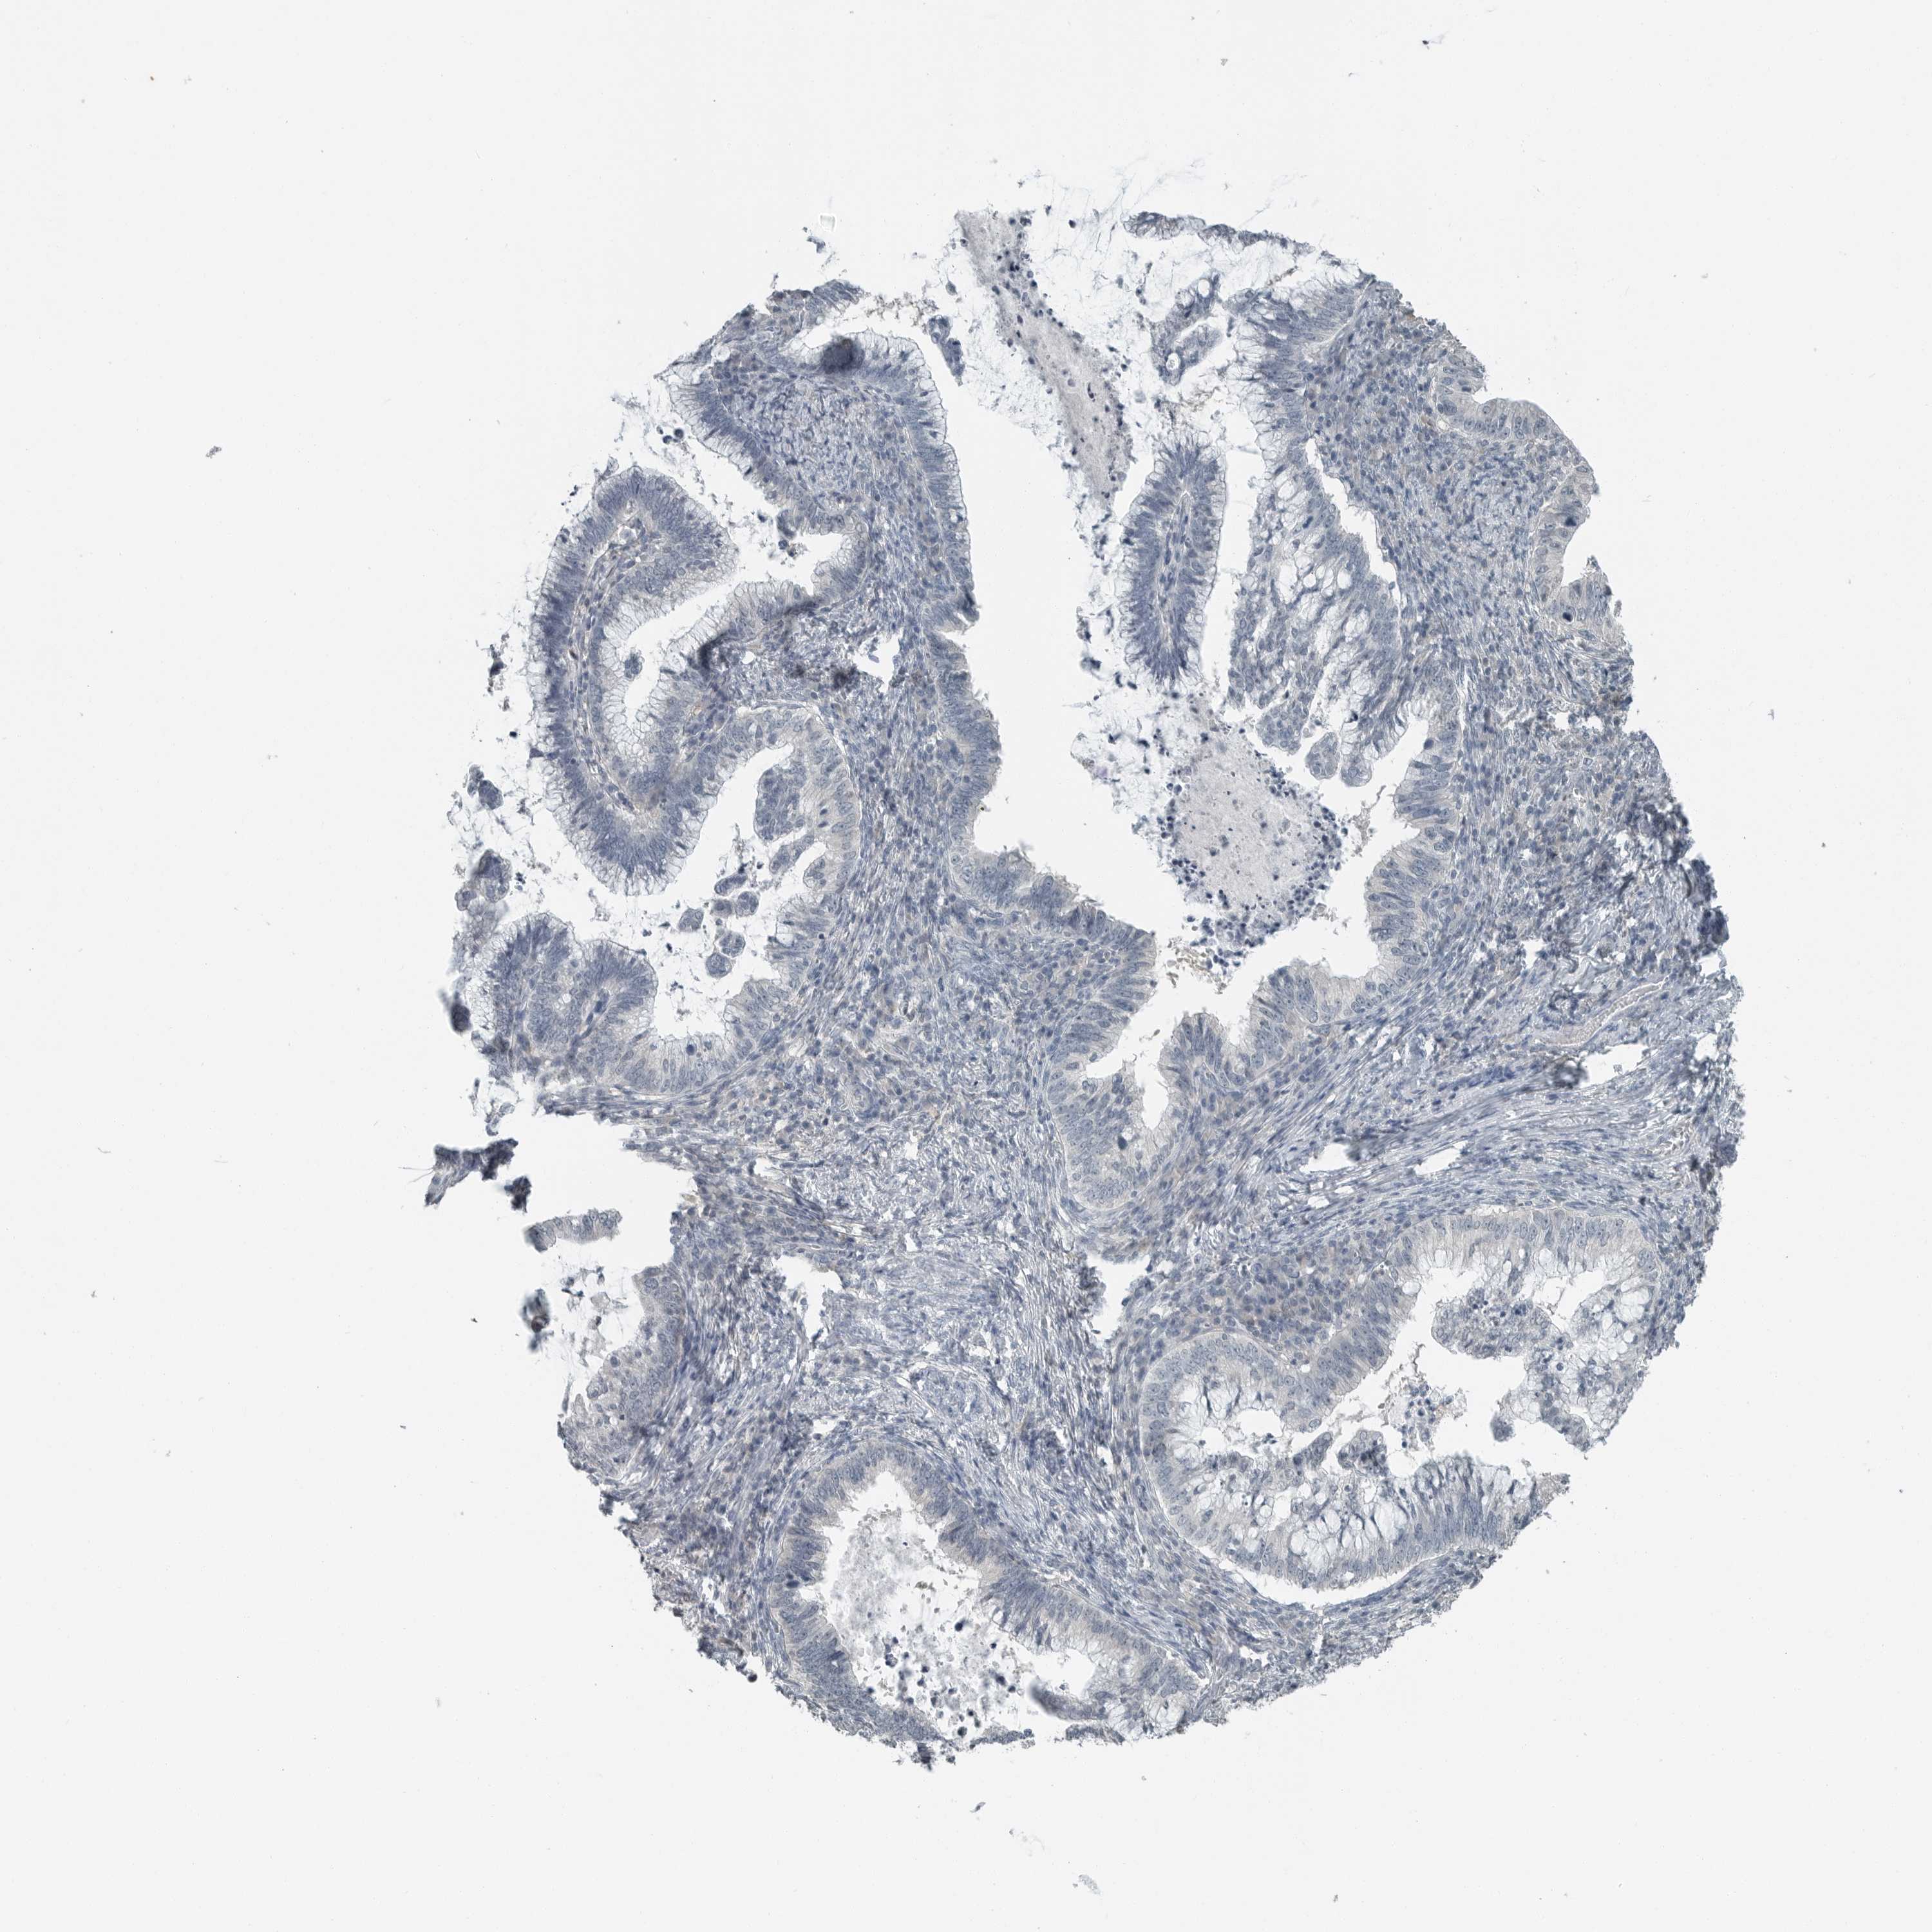

CERVICAL CANCER - Protein expressioni

A mouse-over function shows sample information and annotation data. Click on an image to view it in a full screen mode. Samples can be filtered based on level of antibody staining by selecting one or several of the following categories: high, medium, low and not detected. The assay and annotation is described here.

Note that samples used for immunohistochemistry by the Human Protein Atlas do not correspond to samples in the TCGA dataset.

Antibody stainingi

Antibody staining in the annotated cell types in the current human tissue is reported as not detected, low, medium, or high, based on conventional immunohistochemistry profiling in selected tissues. This score is based on the combination of the staining intensity and fraction of stained cells.

Each image is clickable and will lead to virtual microscopy that enables deeper exploration of all samples and also displays staining intensity scores, fraction scores and subcellular localization as well as patient and tissue information for each sample.

Antibody HPA021176

Antibody HPA021177

Antibody HPA027736

Squamous cell carcinoma, NOS

Adenocarcinoma, NOS